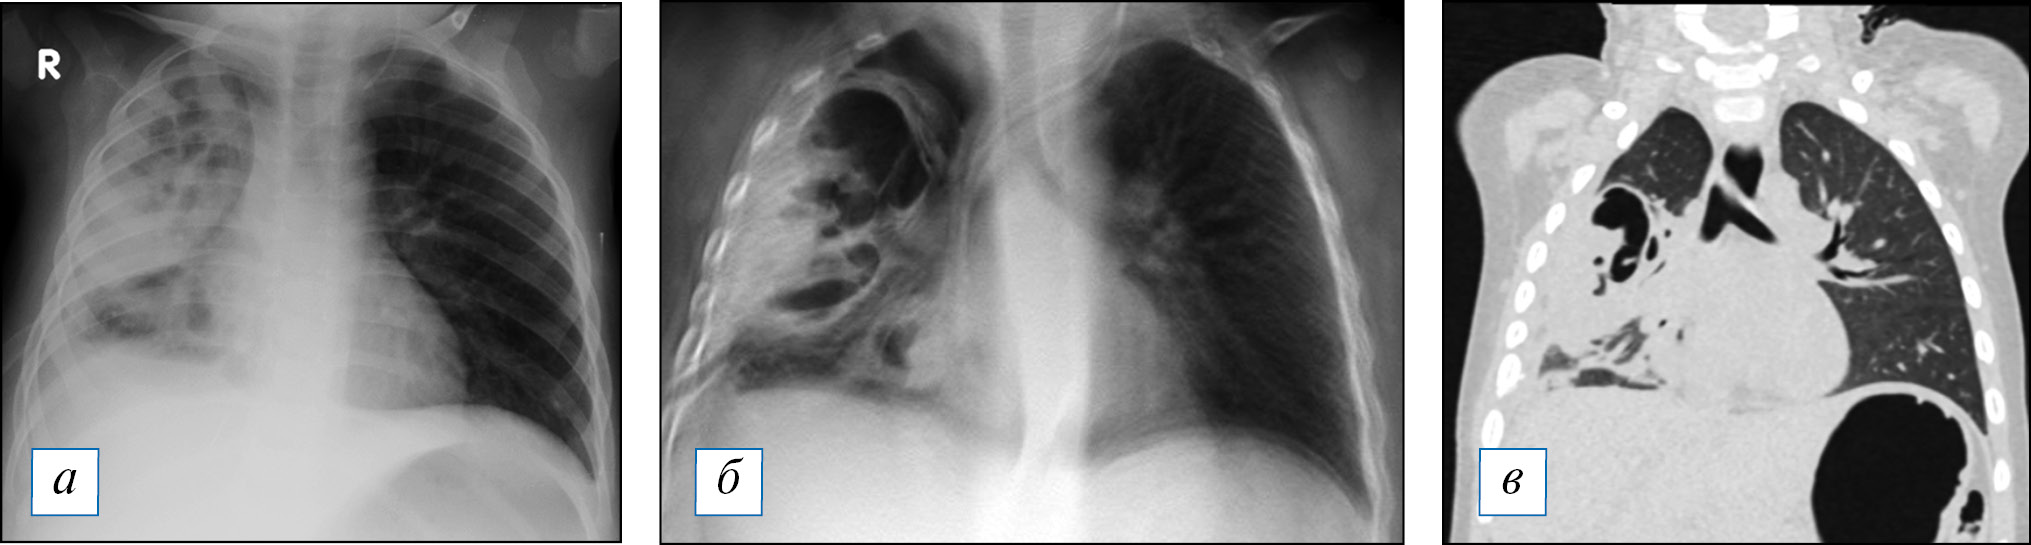

Рис. 2. Результаты лучевого обследования пациентки А., 16 лет. При рентгенографии (а) на 4-е сут заболевания диагностирована нижнедолевая пневмония справа. В ходе томосинтеза (б) визуализированы очаги деструкции в виде округлых очагов просветления в нижней и средней доле справа, число, размер и локализация которых были впоследствии подтверждены методом мультиспиральной компьютерной томографии. / Fig. 2. Results of the X-ray examination of the patient A., 16 years old. Radiografically on the 4th day of the onset of disease was diagnosed lower lobe pneumonia on the right (a). During tomosynthesis (б), foci of destruction were visualized round foci of enlightenment in the lower and middle lobes on the right lung. The number, size and localization of which were confirmed by multispiral computed tomography later.

Рис. 3. Результаты проведенного в сопоставимые сроки лучевого обследования пациента Д., 1 год 8 мес, с субтотальной правосторонней деструктивной пневмонией: а — рентгенография; б — томосинтез; в — мультиспиральная компьютерная томография. / Fig. 3. Results of the different examination in comparable periods of the patient D., 1 year 8 months, with subtotal right-sided destructive pneumonia: a — radiography; б — tomosynthesis; в — multispiral computed tomography.